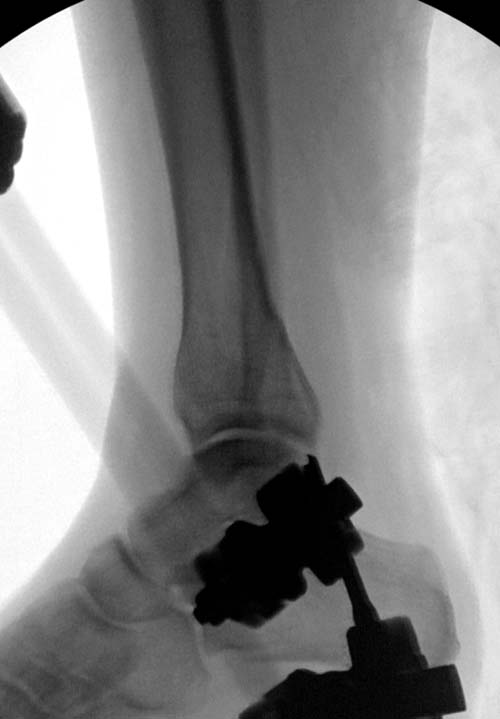

Первый случай, где перелом в результате падения с небольшой высоты, где мортиз рентген снимок показал отстутствие укорочения наружной

лодыжки и КТ срезы подсказали направления атаки. После такой фиксации нет надобности в гипсовой повязке, брейс и через две недели движения в

суставе без нагрузки.

Второй случай в результате скоростной травмы, кроме пилона, вовлечение других органов! Отек при поступлении и открытый перелом на другой стороне. В таких случаях нет смысла спешить, и временный наружный фиксатор на несколько дней. После спадения отека фиксация передне-наружной пластиной. Реабилитация - ранние движения, без нагрузки.